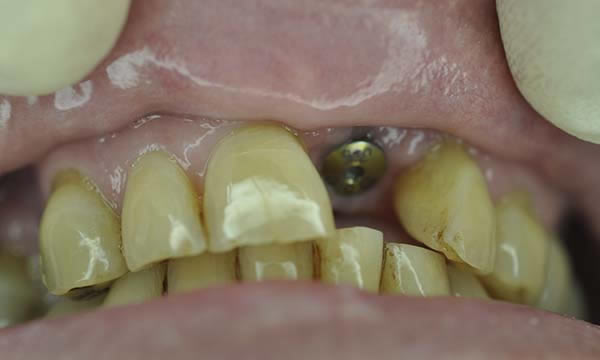

Case H

This case is a collaboration between ourselves and a specialist periodontist based in the referring practice. A case of patience, where a patient wanted to be rid of his un-retentive denture replacing the UL1 while stabilising his periodontal disease with improved home care and treatment from a specialist periodontist.

After approximately 12 months of periodontal therapy, the patient was deemed stable enough by the specialist periodontist to undergo implant treatment. An Astra EV implant was placed and a well shade matched zirconia crown was luted to an Atlantis abutment. Digital SLR pictures were used to provide the lab technician with appearance detail of the neighbouring dentition, to allow the technicians at Smile Dental Laboratory to introduce 'accents' and a realistic and seamless look to the final zirconia prosthesis.

During Treatment